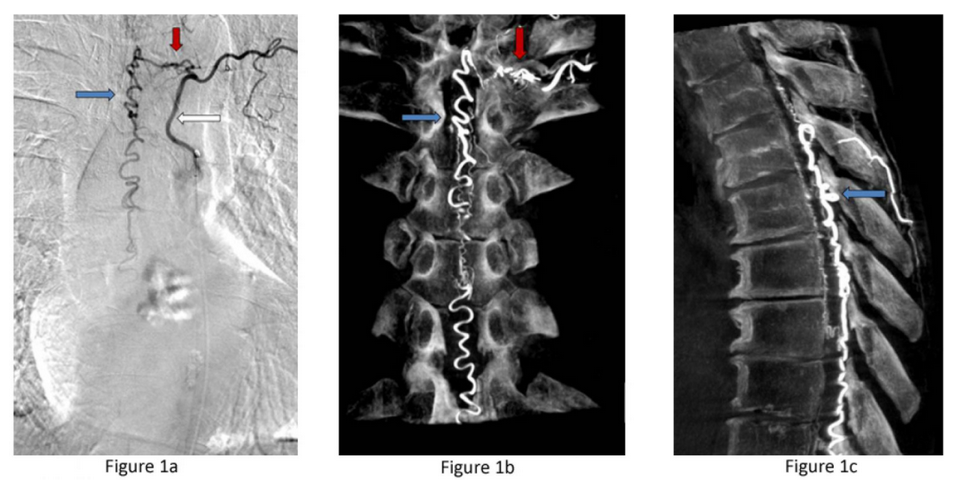

Figure 1a: Type I dural AV fistula – spinal angiogram of a left sided spinal artery (white arrow) showing an abnormal connection (red arrow) with a spinal vein that has become abnormally enlarged (blue arrow). Figure 1b: Similar view of the same fistula using a 3D flat panel CTA reconstruction showing greater detail of the abnormal artery-venous connection within the nerve root dural sleeve (red arrow) and enlarged vein within the spinal canal (blue arrow). Figure 1c: Side or sagittal view of the same fistula showing the enlarged vein (blue arrow) along the back wall of the spinal canal behind the spinal cord.

Spinal Dural Arteriovenous Fistulas (Type I): These lesions account for the 70% of spinal malformations and are the result of an abnormal connection between a dural artery and a vein within the spinal canal dura. The abnormal connection between the high pressure system of arteries and the low pressure network of veins creates high pressure in the vessels draining the spinal cord. The elevated pressure prevents blood leaving the spinal cord and damages the cord over time. Spinal dural fistulas occur spontaneously in adults and are neither inherited nor congenital. These wounds do not break or ooze blood, making them excellent candidates for surgical treatment.